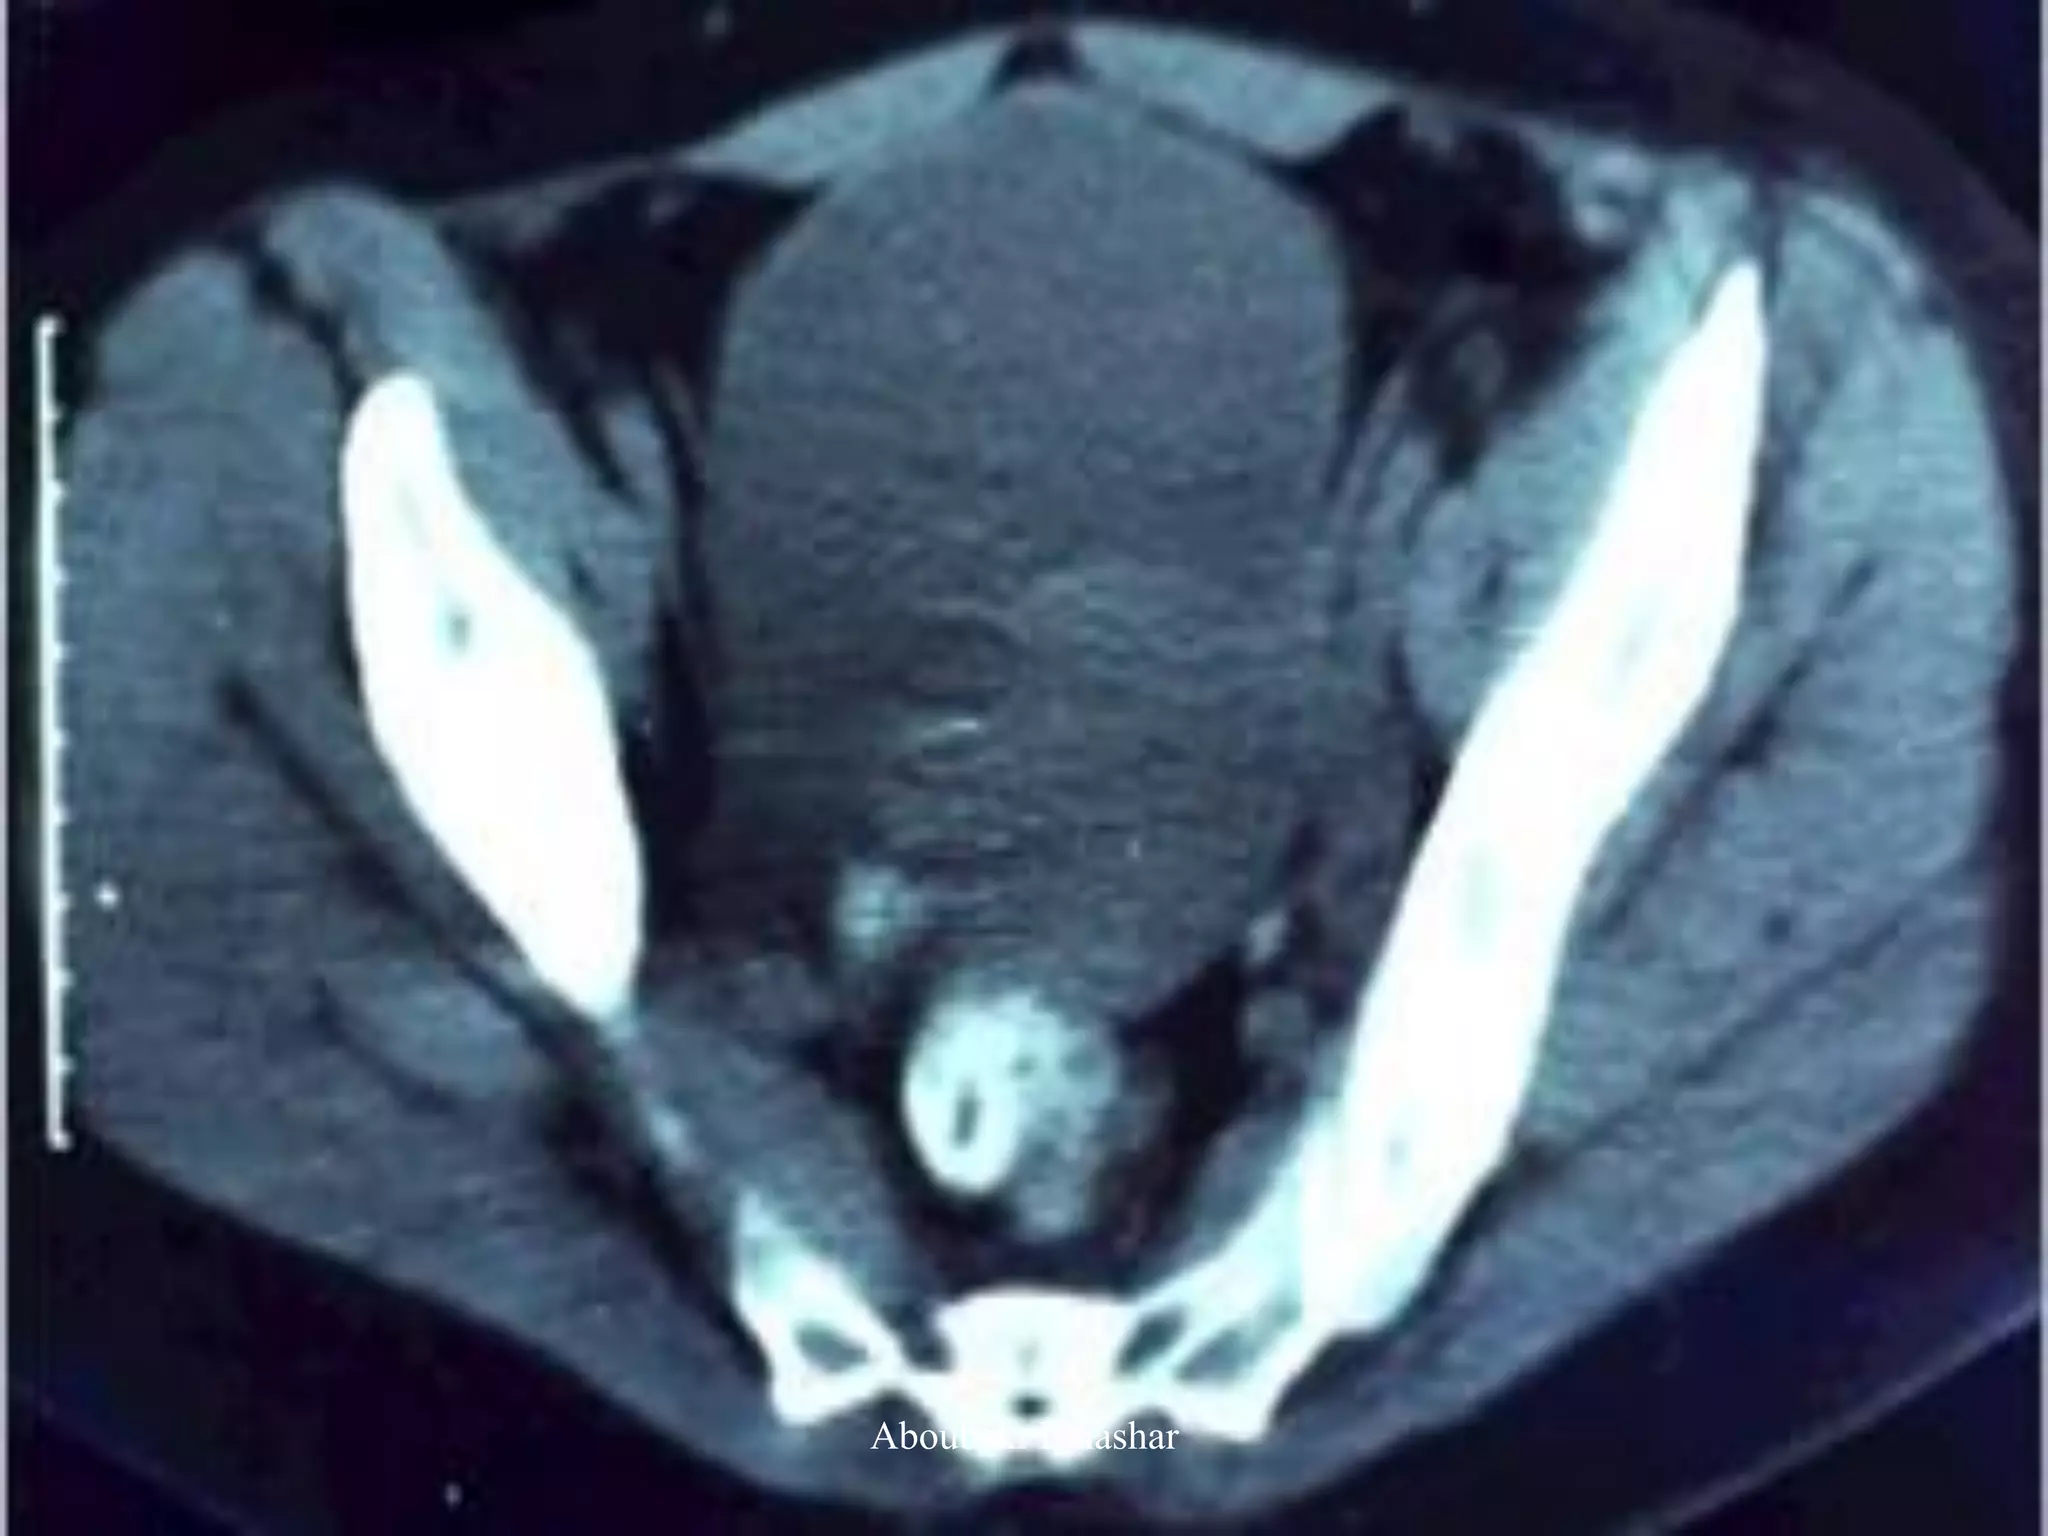

3. CT:

has been replaced by MRI

poor specificity

high radiation dose

An important role for the CT scan with contrast is to

detect ureteral involvement and possible renal

insufficiency.